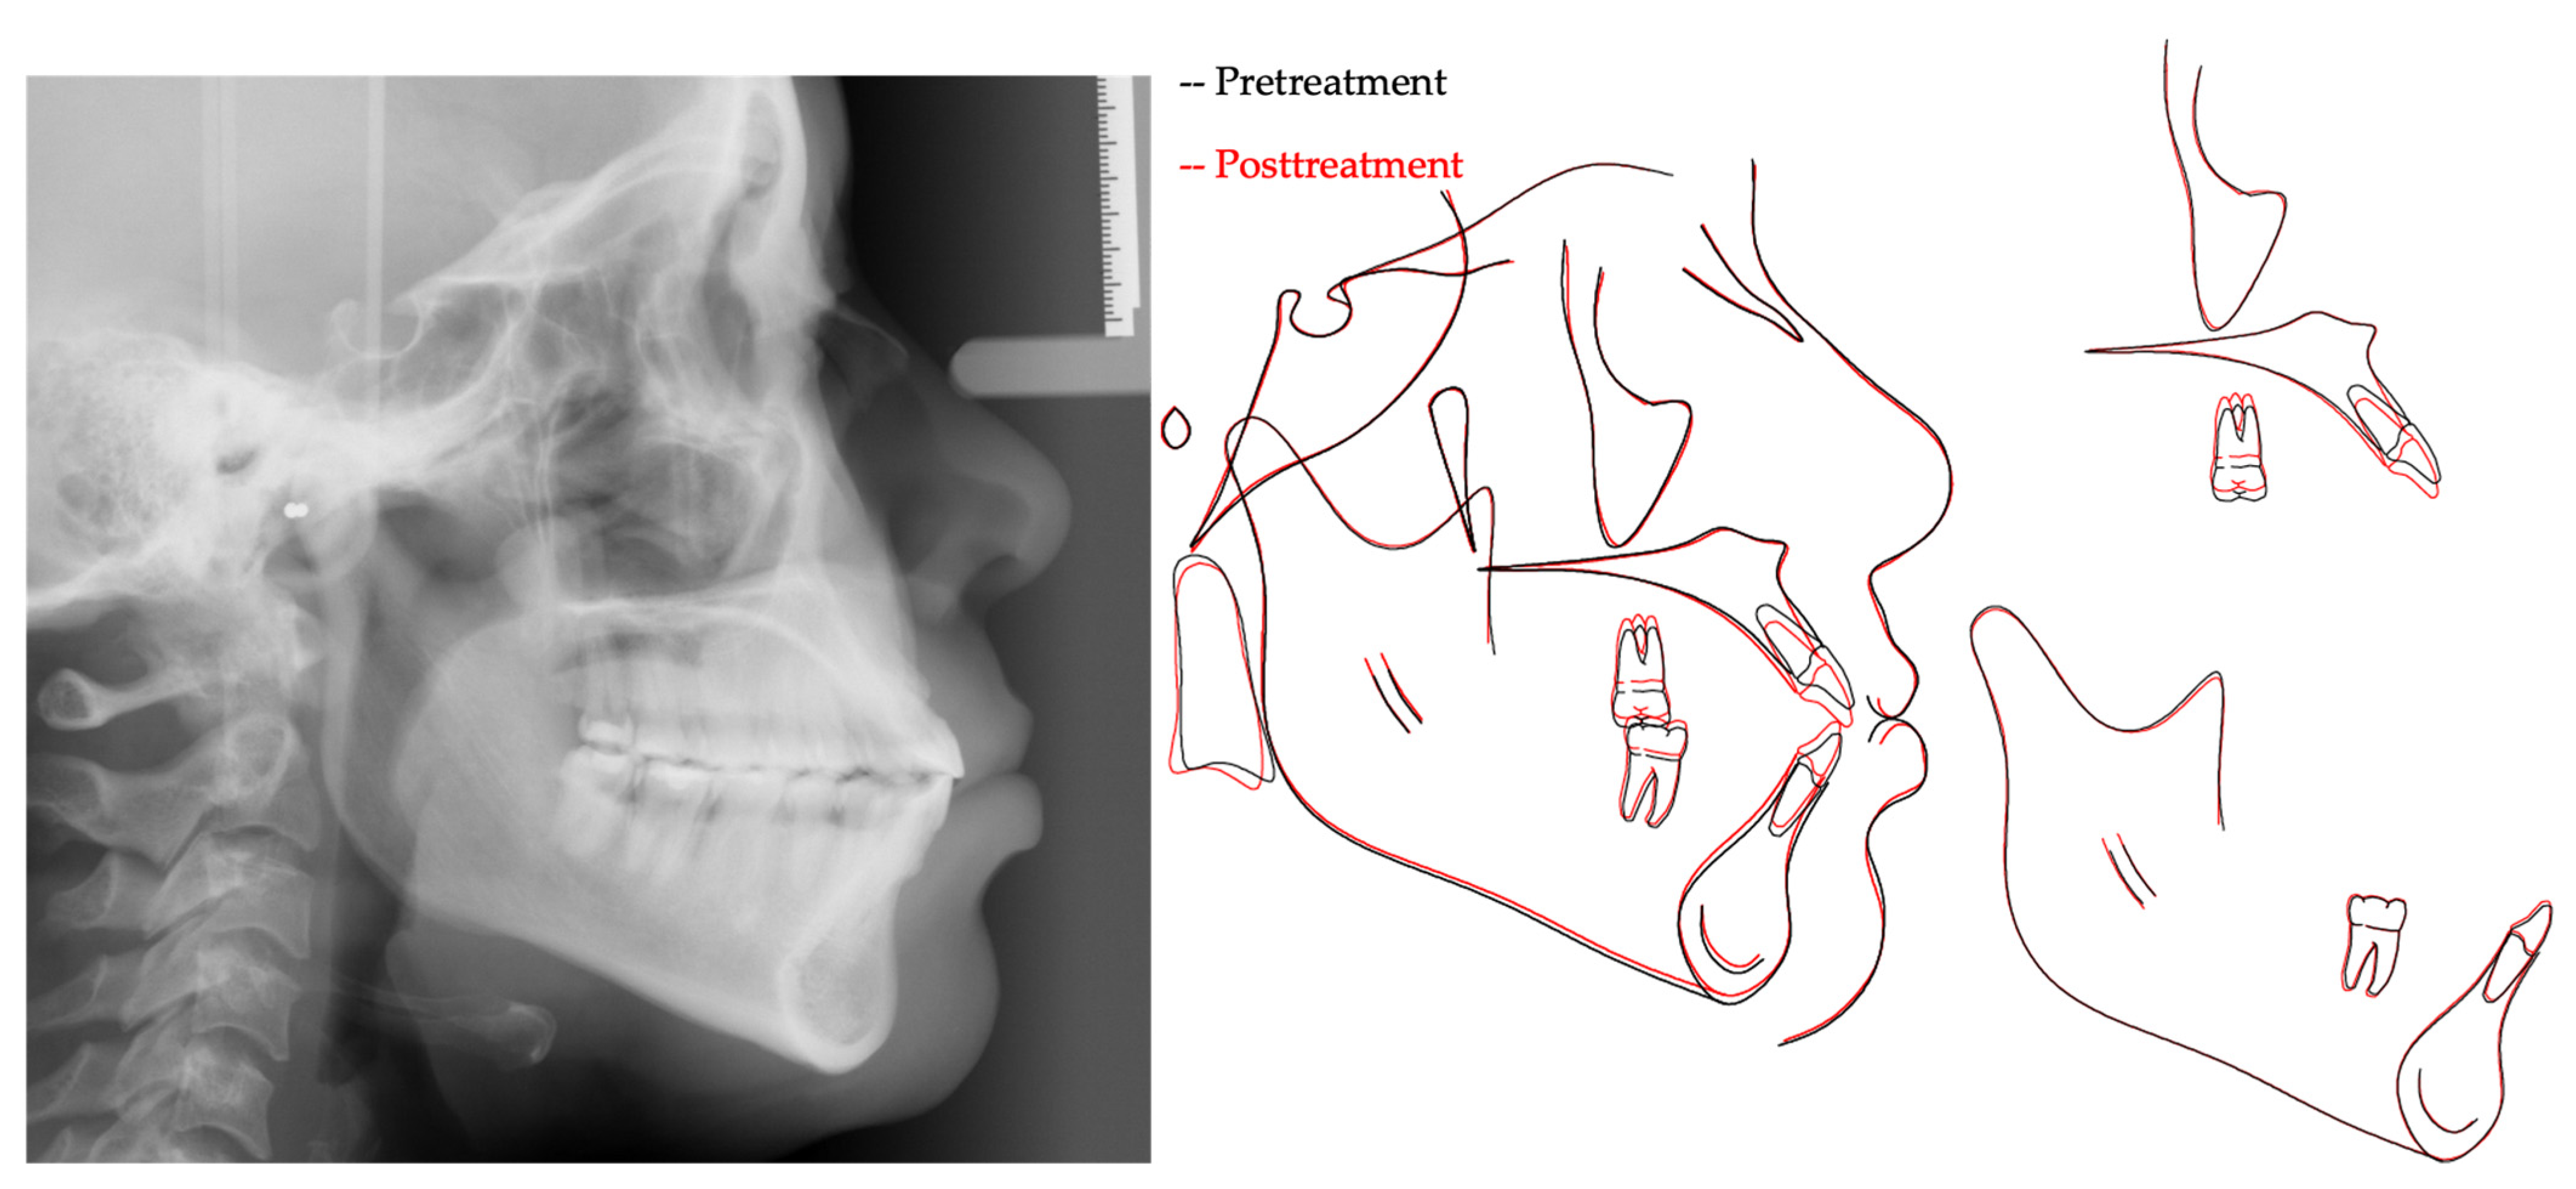

2. Case Presentation

3. Treatment Results

| Measurement | A (Initial) | B (Final) | Difference (A-B) |

|---|---|---|---|

| SNA° | 89.6 | 89.3 | 0.3 |

| SNB° | 84.7 | 84.6 | 0.1 |

| ANB° | 4.9 | 4.7 | 0.2 |

| SN-MP° | 38.7 | 37.5 | 1.2 |

| FMA° | 26.3 | 25.3 | 1.0 |

| UI TO NA mm | 6.8 | 5.7 | 1.1 |

| UI TO SN° | 119.6 | 115.1 | 4.5 |

| LI TO NB mm | 11.0 | 10.5 | 0.5 |

| LI TO MP° | 97.8 | 96.0 | 1.8 |

| U Lip to E-Line | −1.3 | −1.3 | 0.0 |

| L Lip to E-Line | 2.7 | 2.5 | 0.2 |